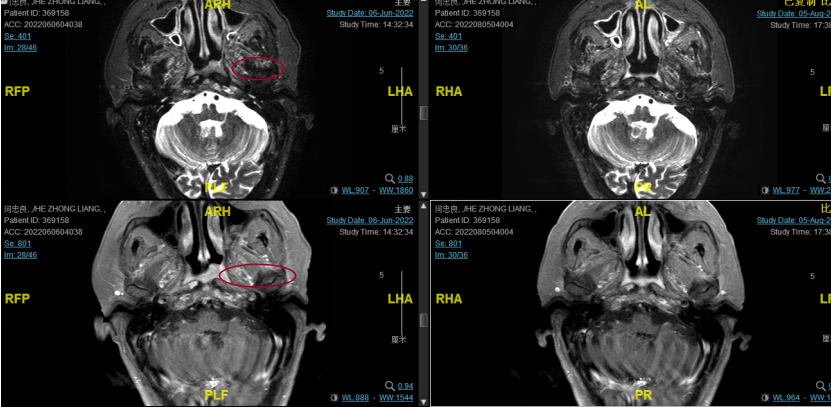

后患者至江苏省肿瘤医院放疗科就诊,2022-06-06完善头颅MR检查:

修正诊断:鼻咽癌T3N1M0,Ⅲ期。

2022-08-05(放疗近结束)复查MR,疗效评价:CR。鼻咽部肿物及咽后转移淋巴结颈部转移淋巴结均达到CR。